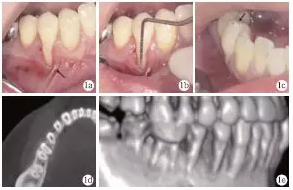

臨床檢查發(fā)現(xiàn),患者全口牙齦無明顯紅腫,探診深度1~4mm,BOP(+)<15%;#44頰側牙頸部充填物,頰側可見9mm齦退縮,超過膜齦聯(lián)合,僅存小于1mm的角化齦,且近中見系帶附著,近遠中齦乳頭均存在輕度退縮(圖1a、1b);正中咬合時可捫及#44功能性動度,頰尖舌斜面可見咬合高點(圖1c)。術前CT見#44頰側牙槽骨吸收達根尖1/3,鄰面擴展達根間區(qū),鄰面牙槽骨高度降低(圖1d、1e)。根據(jù)臨床檢查和CT檢查,診斷為#44Miller Ⅲ°牙齦退縮。

圖1 術前臨床及X線檢查